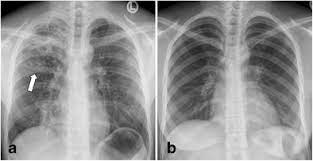

Case contributed by dr brenda lee solorzano frontal chest x ray shows bilateral micronodular insterstitial effusion. Tuberculosis, a disease that used to be common in the uk and other western countries, was the doctor who examined mr abas suspected lung disease. For decades, tuberculosis (tb), a potentially serious infectious lung disease, continues to be a leading cause of worldwide death. Tb is an airborne disease caused by the bacteria mycobacterium tuberculosis and mycobacterium bovis. Thus chest x rays are neither specific nor sensitive and so remain a supplement to microbiological tests such as microscopy pcr and culture. A practical manual for preventing tb, 2011. The samples are tested for tb bacteria. From point ai to point tb:

From tb suspects attending a chest clinic in nairobi, kenya, three sputum specimens were examined for zn and culture (lowenstein jensen). The contagious disease of tuberculosis not only attacks the lungs but also can affect other organs such as the kidney, spine and brain. Therefore, all persons with chest radiographic findings suggestive of tb. Tuberculosis a manual for medical students. Tb is an airborne disease caused by the bacteria mycobacterium tuberculosis and mycobacterium bovis. Tuberculosis without established localization the greatest difficulties arise at diagnosing tubercular intoxication and small formsof lymphatic nodes. This manual would not have been possible without the comments and suggestions of colleagues with considerable. Tuberculosis of intrathoracic lymphatic nodes 3.2.3. At the description of these shadows it is. Tuberculosis is an infectious disease that causes inflammation, the formation of tubercles and other growths within tissue, and can cause tissue death. For decades, tuberculosis (tb), a potentially serious infectious lung disease, continues to be a leading cause of worldwide death. Left apical bronchiectasis at the level of. The samples are tested for tb bacteria.

Abnormalities on chest radiographs may be suggestive of, but are never diagnostic of tb, but can be used to rule out pulmonary tb. From point ai to point tb: Culture was used as gold standard. Other views (lateral or lordotic). This is a matter of definition.

Tuberculosis, a disease that used to be common in the uk and other western countries, was the doctor who examined mr abas suspected lung disease. Other views (lateral or lordotic). Left apical bronchiectasis at the level of. A practical manual for preventing tb, 2011. Tb is an airborne disease caused by the bacteria mycobacterium tuberculosis and mycobacterium bovis. The contagious disease of tuberculosis not only attacks the lungs but also can affect other organs such as the kidney, spine and brain. For decades, tuberculosis (tb), a potentially serious infectious lung disease, continues to be a leading cause of worldwide death. The samples are tested for tb bacteria. This is a matter of definition. This manual would not have been possible without the comments and suggestions of colleagues with considerable. From tb suspects attending a chest clinic in nairobi, kenya, three sputum specimens were examined for zn and culture (lowenstein jensen). From point ai to point tb: On radiograph tubercular lesions of lung parenxyma, stroma comes to light as shadows (densities, consolidations).

At the description of these shadows it is. Tuberculosis a manual for medical students. Left apical bronchiectasis at the level of. On radiograph tubercular lesions of lung parenxyma, stroma comes to light as shadows (densities, consolidations). A practical manual for preventing tb, 2011.